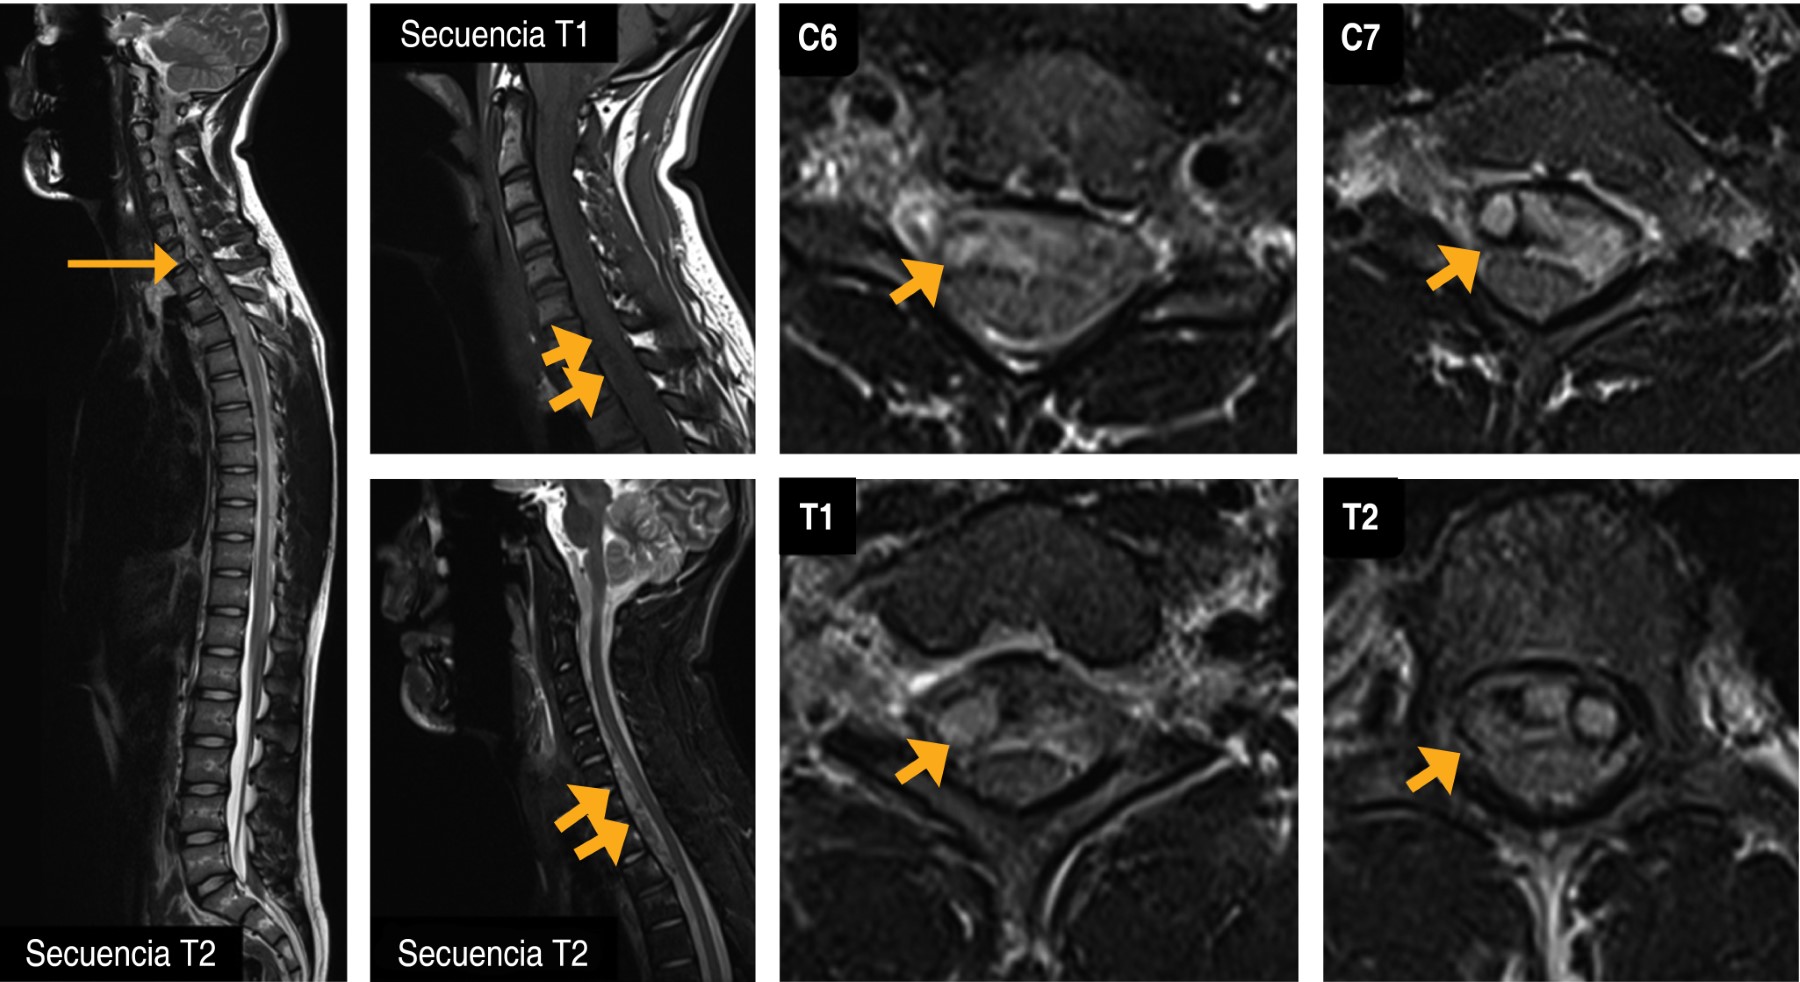

Introduction: spinal subdural hemorrhage is rare and potentially devastating. It occurs most frequently in lumbar puncture, spinal anesthesia, therapeutic anticoagulation and coagulation disorders, and spinal tumors or vascular malformations. Case presentation: we describe a case of a 17-year-old man with intracranial and cervicothoracic hemorrhage secondary to acute trauma with neurological deficit in whom surgical treatment had a good outcome. Conclusions: It has been shown that surgical intervention, as in all acute spinal cord compression, surgical treatment must be rapid above all and is associated with neurological deterioration (motor or sensory). An expectant management is possible if early neurological recovery occurs in the context of a good neurological examination on admission with MRI follow-up.

Figure 1